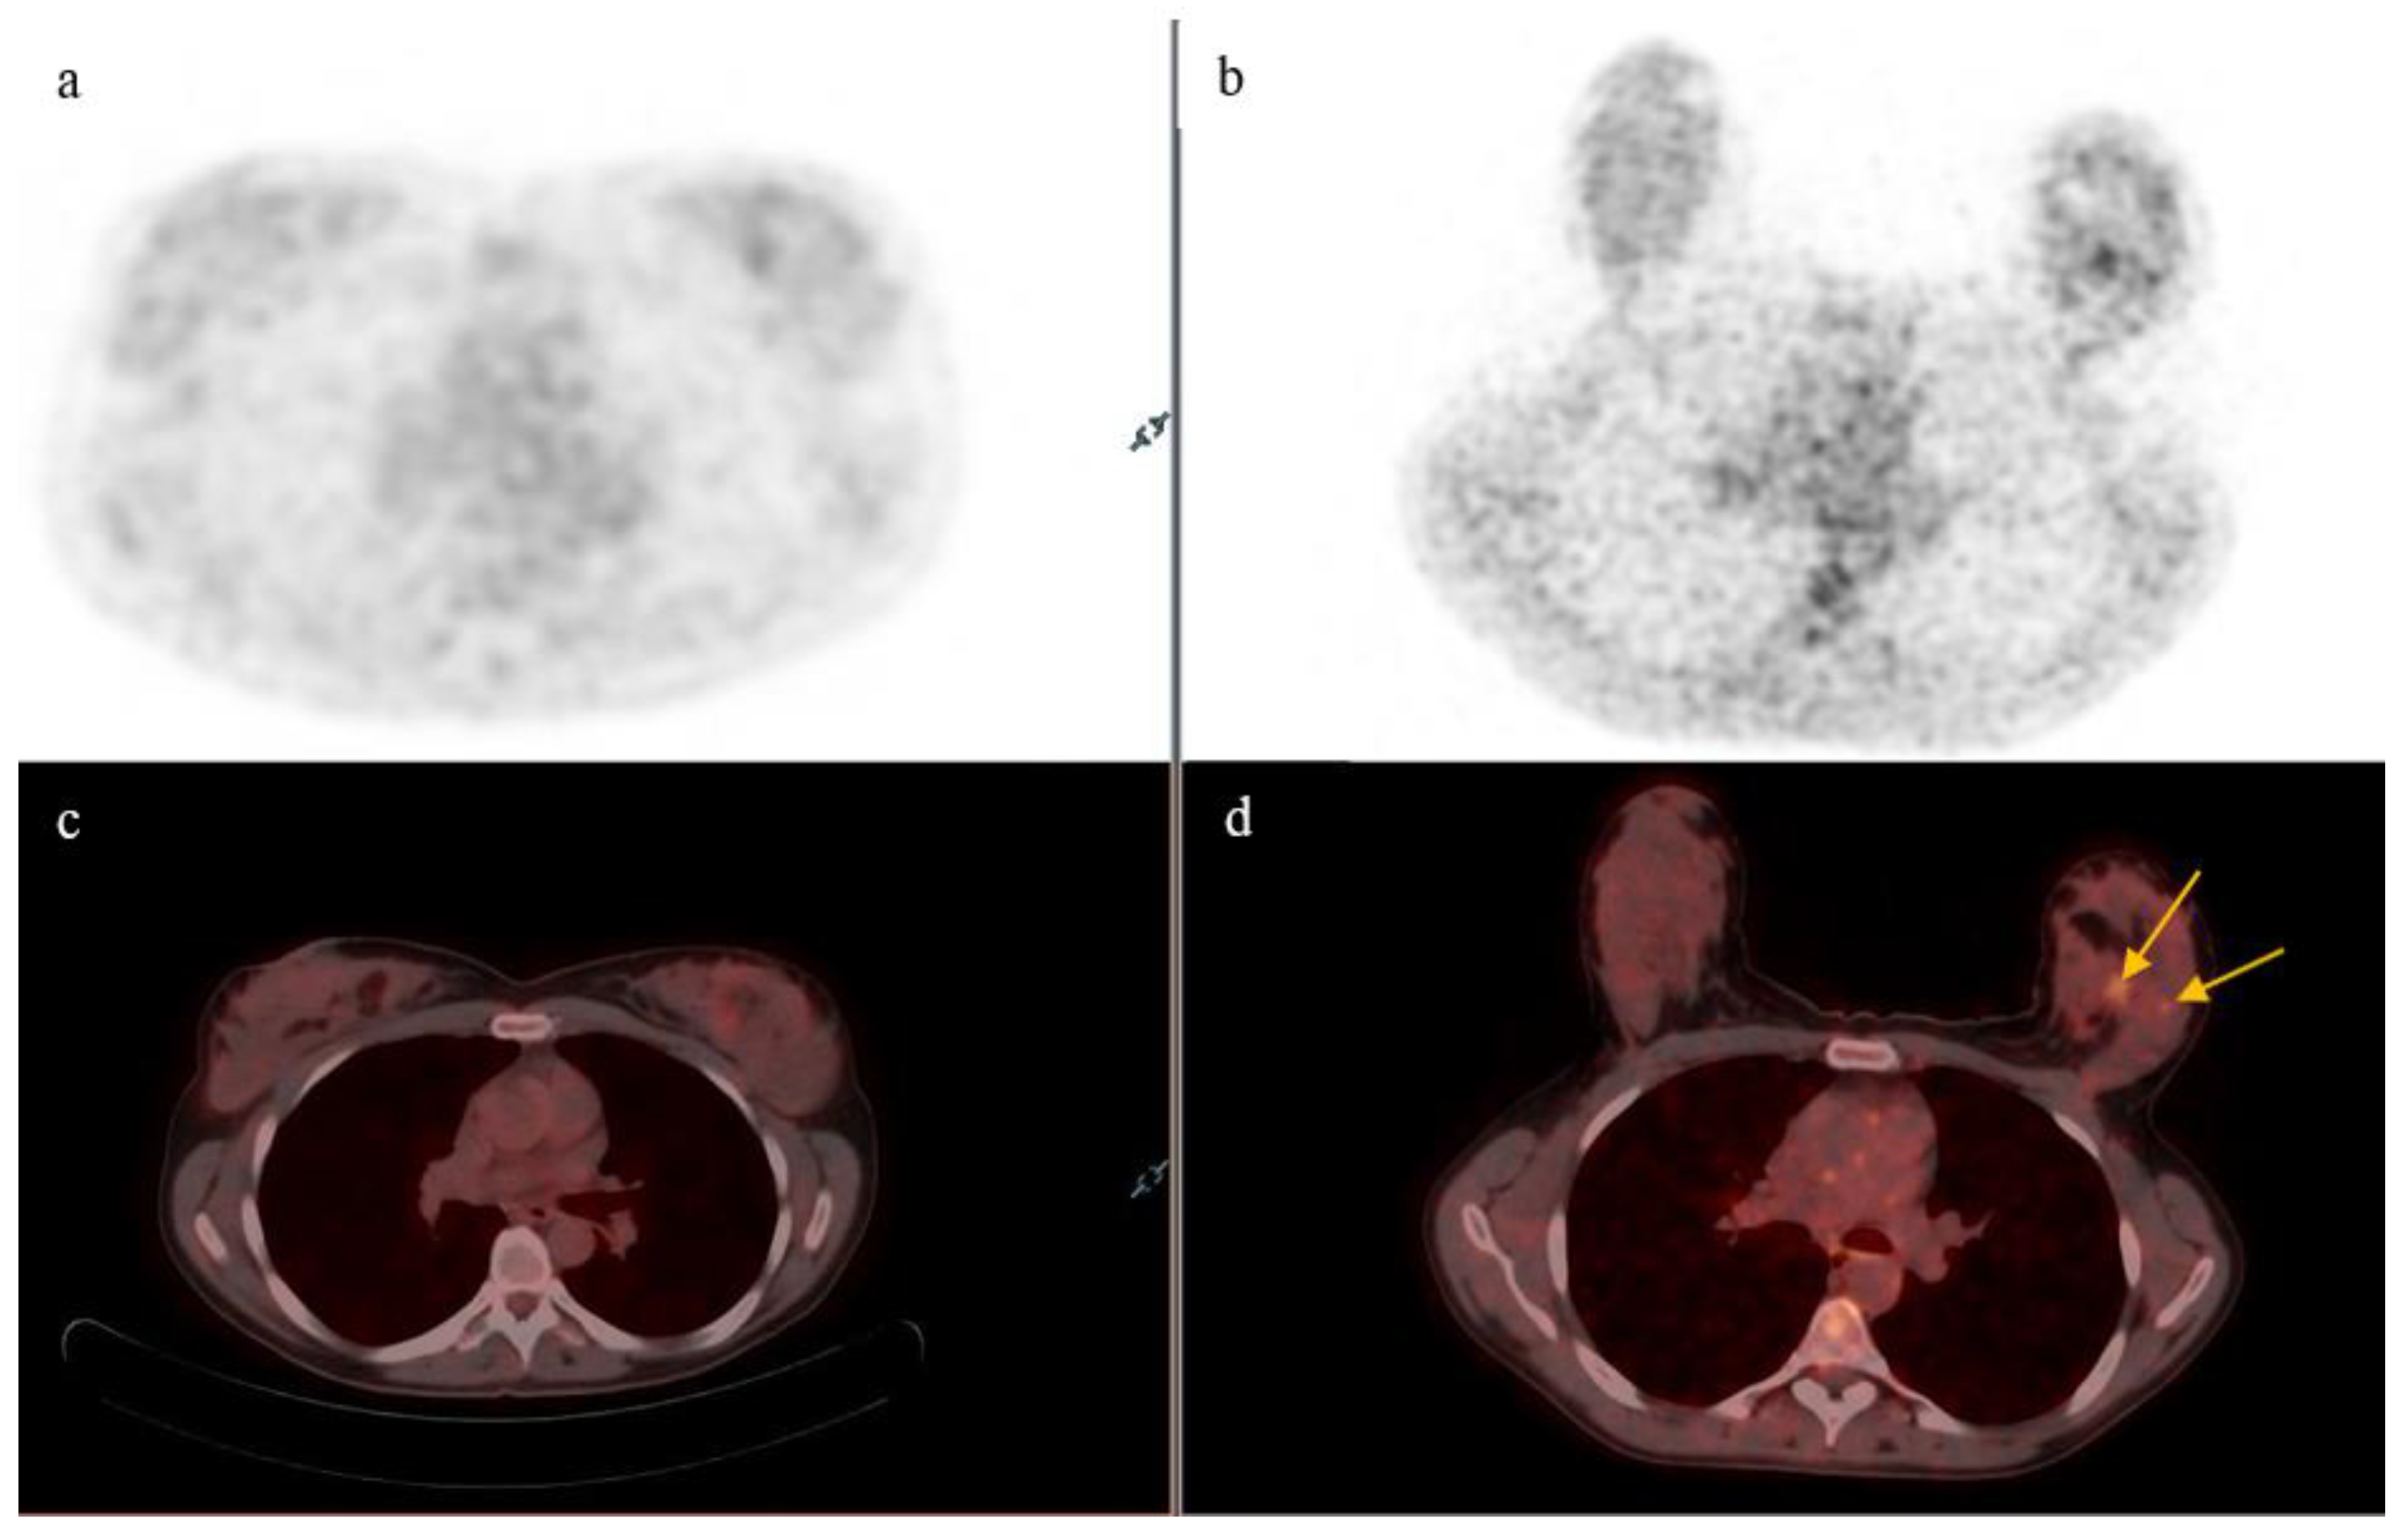

- On supine position acquisition, primary breast lesions were missed in three patients, all of which were detected on prone position. One such example is seen in Figure 2,